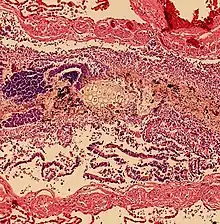

Pulmonary aspiration of particulate matter may result in acute airway obstruction which may rapidly lead to death from arterial hypoxemia.[2]

Pulmonary aspiration of acidic material (such as stomach acid) may produce an immediate primary injury caused by the chemical reaction of acid with lung parenchyma, and a later secondary injury as a result of the subsequent inflammatory response.[2]

Pulmonary aspiration may be followed by bacterial pneumonia. Community-acquired aspiration pneumonia is usually caused by anaerobic bacteria, whereas hospital-acquired aspiration pneumonia is more often caused by mixed flora, including both aerobic and anaerobic bacteria.[2]